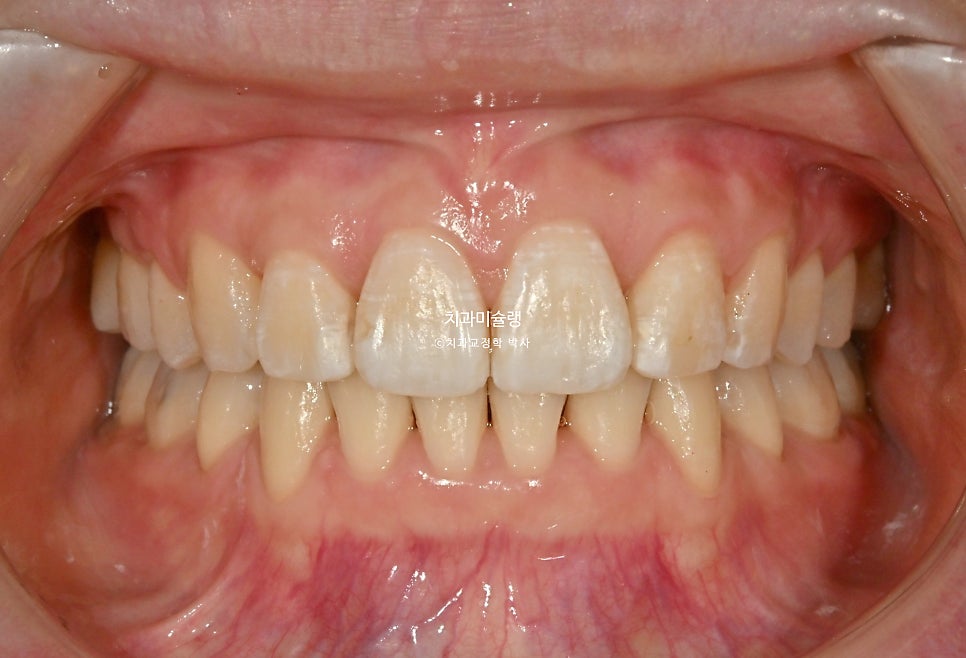

이제 전후사진 비교 보겠습니다.

2022.12-2026.02

환자분이 가장 고치고 싶어했던 앞니각도는 깔끔해졌습니다.

앞니 돌출로 인해 입이 편하게 안다물리던 입술부전증이 해소되어 위아래 입술이 편하게 다물리고

입술 사이로 빼꼼 보였던 앞니가 이제는 보이지 않습니다.

스마일라인은 아랫입술과 평행을 이루며

입술 돌출은 적당히 해소되었습니다.